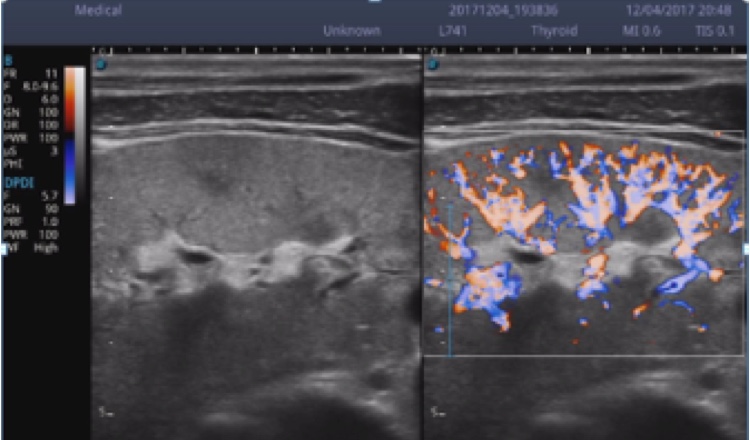

X5采用前端的超声专用芯片,将台式机大规模集成电路完美压缩在笔记本超声的精巧下,提高了系统的运算速度,加载μ-Scan微米成像、脉冲反相谐波等技术,带来优异的临床表现,清晰呈现高分辨率二维图像和层次丰富的血流图像

X5具备实时宽景成像、穿刺增强、彩色M型、组织多普勒等多种高级成像功能,全方位满足多个科室的诊断需求,整机系统向智能化跨越